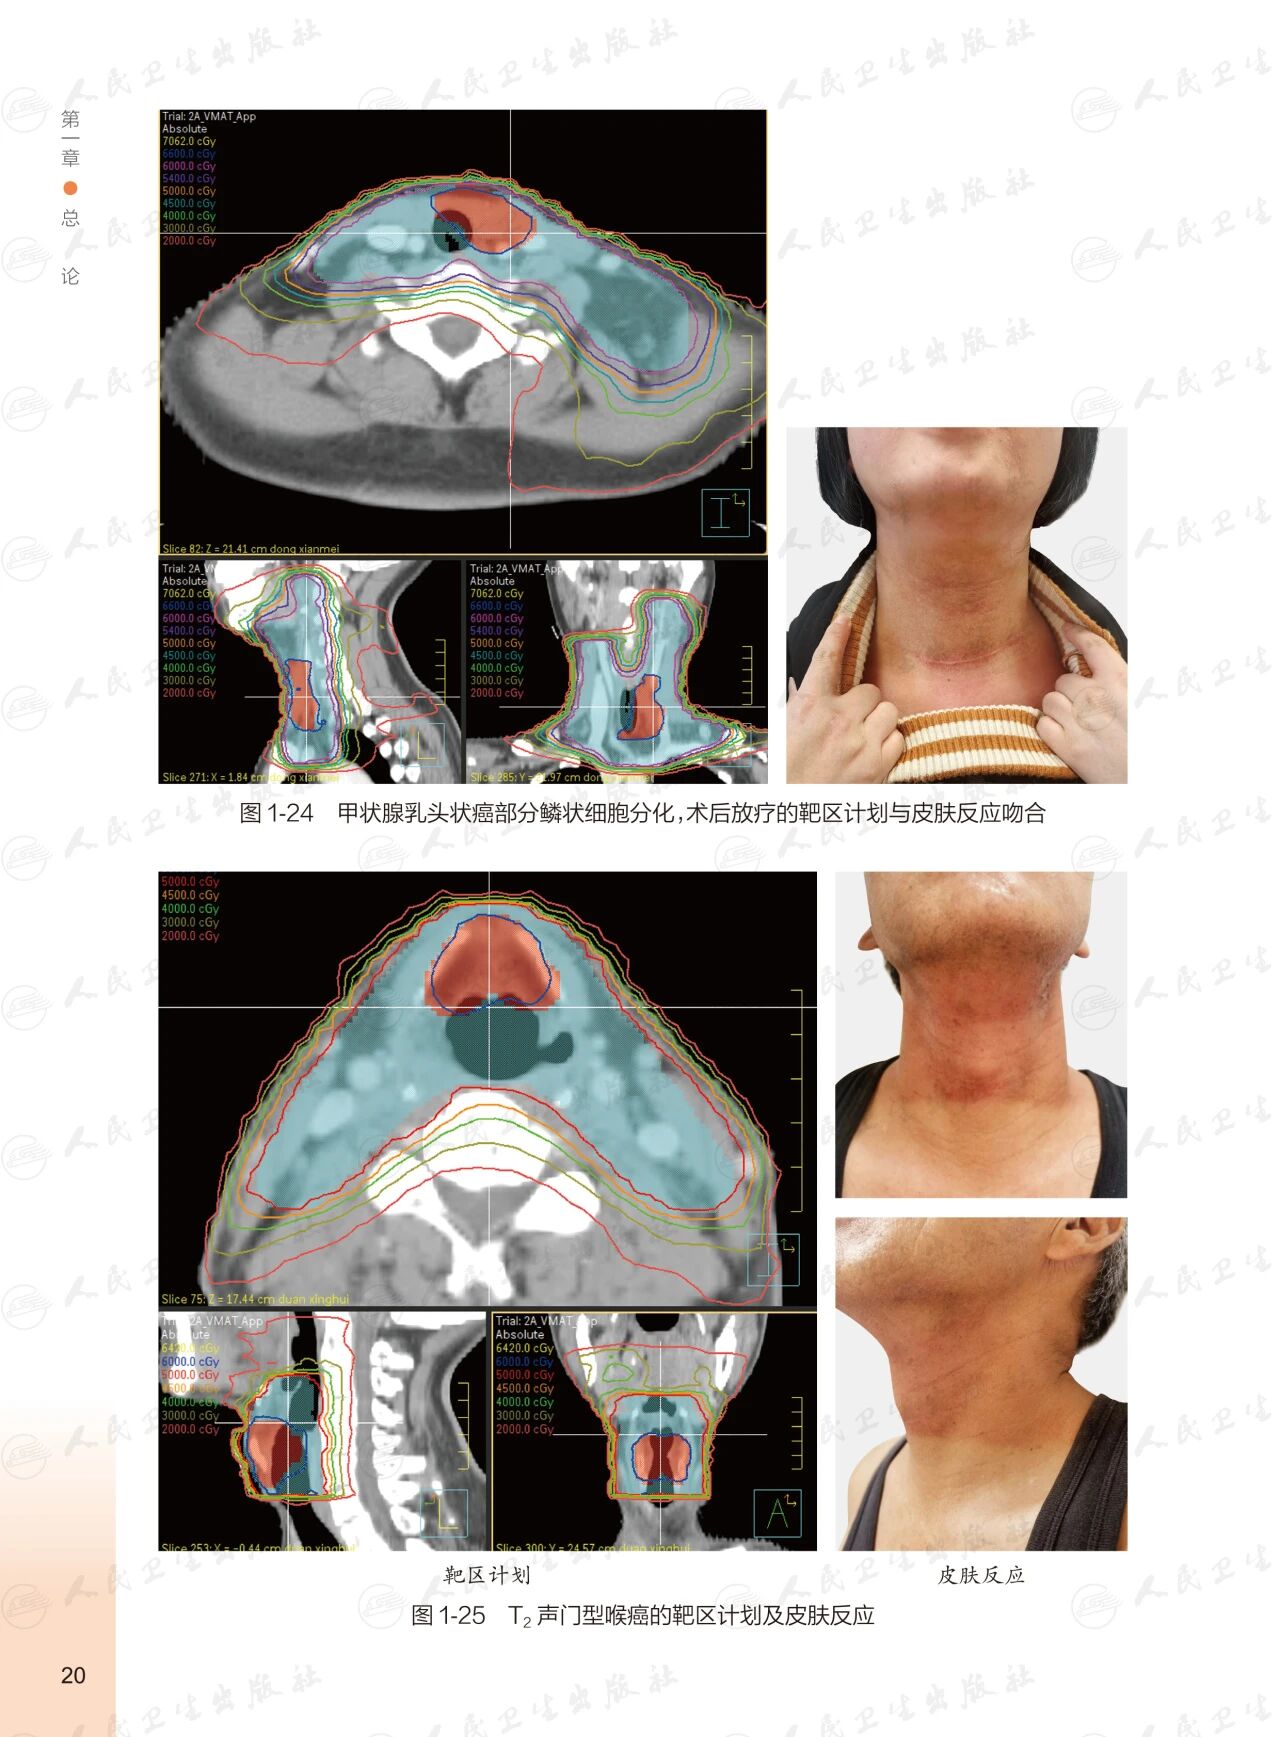

《头颈部肿瘤放射治疗图谱》

——不止是图谱,更是随唤随应的临床良师